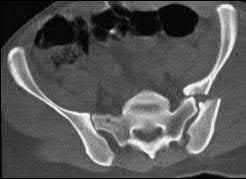

A 35 year-old female presents after prolonged extrication from a motor vehicle collision complaining of severe pelvic pain. Physical examination reveals diminished perianal sensation. She is otherwise neurologically intact. Figures A through D are radiographs and representative CT cuts of her injury. Which of the following nerve roots has likely been injured by the acute trauma?

The clinical scenario is consistent with a high-energy sacral fracture. The radiographs in figures A and B demonstrate a sacral fracture with posterior displacement of the right hemipelvis seen on the inlet view. Figures C and D are axial and sagittal CT images which show a displaced fracture of the right

hemisacrum along with a transvere fracture component through the S3 body . Diminished perianal sensation is concerning for an S2 nerve root injury.